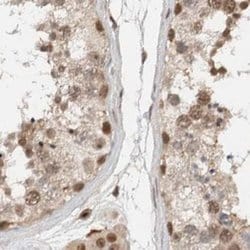

Invitrogen™ ZNF521 Polyclonal Antibody

Brand: Invitrogen™ PA554898

| Immunohistochemistry (Paraffin) | |

| Recombinant protein corresponding to Human ZNF521. Recombinant protein control fragment (Product #RP-93654). | |